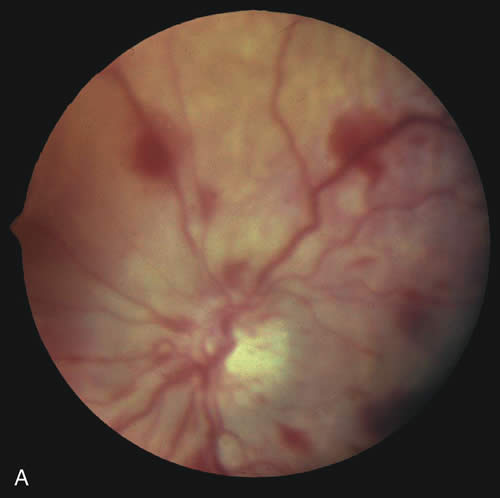

Findings range from a normal fundus to a small number of scattered intraretinal hemorrhages in the posterior pole to massive, confluent hemorrhages from the posterior pole to the ora serrata.(Fig. 10) The hemorrhages may be subretinal, deep intraretinal (dot/blot), nerve fiber layer (flame shaped) or preretinal.19,45 Intraretinal hemorrhages are more common than preretinal or subretinal hemorrhages.32,46 Preretinal hemorrhages must be distinguished from traumatic retinoschisis (see later), which has particular diagnostic significance. White-centered retinal hemorrhages, although classically associated with endocarditis, can occur in any condition that causes retinal hemorrhages, including SBS. Vitreous hemorrhage may be small to massive, and may occur secondary to escape of blood from intraretinal collections or from torn vessels.19 Although vitreous hemorrhage may occur at the time of injury, it may also be a delayed finding occurring 1 to 3 days or more after the initial trauma.47,48

Fig. 10. Retinal hemorrhages in SBS may range from a nonspecific mild posterior pole distribution (10A) to a more characteristic picture of too numerous to count, multiple, extensive intraretinal hemorrhages (in this many with white centers) with subhyaloid hemorrhage (10B, 10C)

The differential diagnosis of retinal hemorrhages in a child is vast. However, if one considers a child with the full spectrum of injuries seen in SBS, including brain, skeletal, and eye findings, most would not dispute that the retinal findings are due to nonaccidental injury. However, in a child with a small number of retinal hemorrhages and without retinoschisis, (Fig. 10A) the diagnosis of SBS may be less clear.